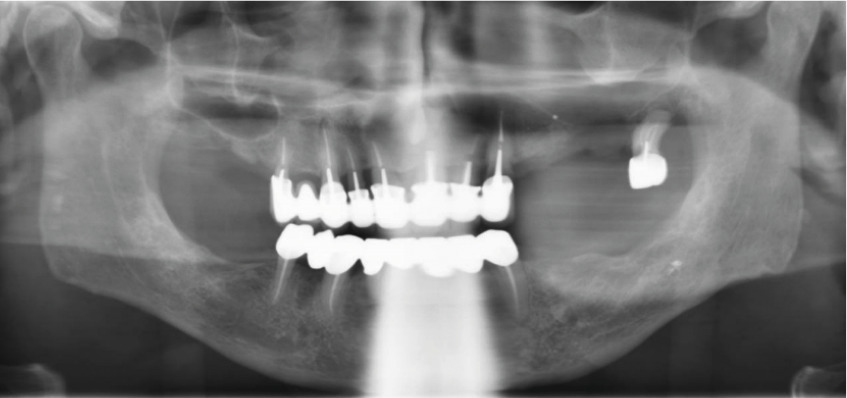

Le bilan d’extension étant négatif, la prise en charge a consisté en une maxillectomie partielle avec avulsion de la dent 27 (fig. 3).